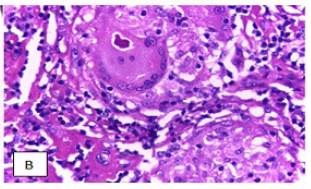

Debido a los anteriores resultados se buscó descartar, en primera medida, un síndrome linfo-proliferativo, por lo cual se solicitó biopsia de ganglio inguinal que reveló una arquitectura alterada por la presencia de gran cantidad de nódulos de aspecto granuloma-toso, sin necrosis de caseificación y constituidos básicamente por abundantes células epitelioides y algunas células gigantes multinucleadas con escasos linfocitos alrededor (fotos 1 y 2).

La inmunohistoquímica del ganglio y los estudios de extensión de médula ósea descartaron enfermedad linfoproliferativa. Posterior a los hallazgos en la biopsia y por la presencia de hipercalcemia asociada a hipercalciuria, se sospechó sarcoidosis. Sin embargo, por el antecedente tuberculoso del paciente se solicitó también radiografía de tórax, en la cual se encontraron opacidades bilaterales, aunque sin derrame pleural.